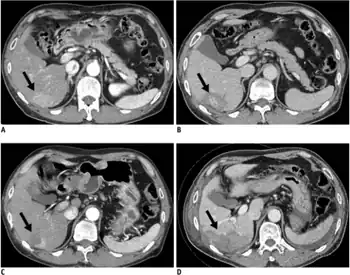

In a person where a higher suspicion of HCC exists, such as a person with symptoms or abnormal blood tests (i.e. alpha-fetoprotein and des-gamma carboxyprothrombin levels),[35] evaluation requires imaging of the liver by CT or MRI scans. Optimally, these scans are performed with intravenous contrast in multiple phases of hepatic perfusion to improve detection and accurate classification of any liver lesions by the interpreting radiologist. Due to the characteristic blood flow pattern of HCC tumors, a specific perfusion pattern of any detected liver lesion may conclusively detect an HCC tumor. Alternatively, the scan may detect an indeterminate lesion and further evaluation may be performed by obtaining a physical sample of the lesion.[16][36]

Ultrasound, CT scan, and MRI may be used to evaluate the liver for HCC. On CT and MRI, HCC can have three distinct patterns of growth:

- A single large tumor

- Multiple tumors

- Poorly defined tumor with an infiltrative growth pattern

A systematic review of CT diagnosis found that the sensitivity was 68% (95% CI 55–80%) and specificity was 93% (95% CI 89–96%) compared with pathologic examination of an explanted or resected liver as the reference standard. With triple-phase helical CT, the sensitivity was 90% or higher, but these data have not been confirmed with autopsy studies.[34]

However, MRI has the advantage of delivering high-resolution images of the liver without ionizing radiation. HCC appears as a high-intensity pattern on T2-weighted images and a low-intensity pattern on T1-weighted images. The advantage of MRI is that it has improved sensitivity and specificity when compared to ultrasound and CT in cirrhotic patients with whom it can be difficult to differentiate HCC from regenerative nodules. A systematic review found that the sensitivity was 81% (95% CI 70–91%) and specificity was 85% (95% CI 77–93%) compared with pathologic examination of an explanted or resected liver as the reference standard.[34] The sensitivity is further increased if gadolinium contrast-enhanced and diffusion-weighted imaging are combined.

MRI is more sensitive and specific than CT.[37]

Liver image reporting and data system (LI-RADS) is a classification system for the reporting of liver lesions detected on CT and MRI. Radiologists use this standardized system to report on suspicious lesions and to provide an estimated likelihood of malignancy. Categories range from LI-RADS (LR) 1 to 5, in order of concern for cancer.[38] A biopsy is not needed to confirm the diagnosis of HCC if certain imaging criteria are met.[16]